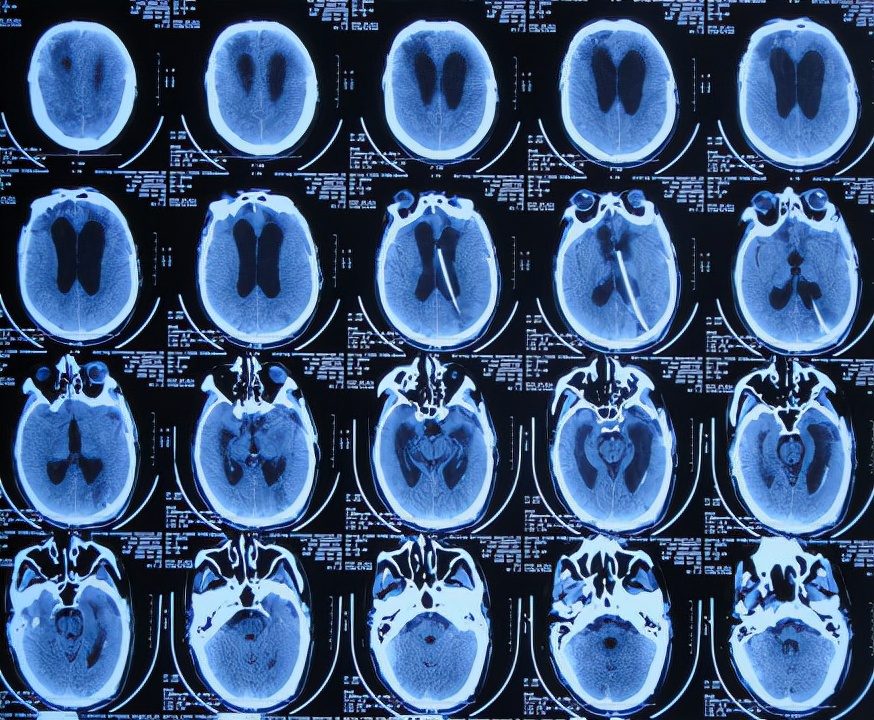

但第1家医院出院后13天即2019年12月4日,出现尿*禁失**,到当地的邯郸市临漳县某医院查头颅CT( 图-13 )后,转给给予开颅手术的医院医生,医生认为与出院时无明显变化,但之后的6天时间内出现走路不稳,大小便*禁失**加重的症状。

图-13: 2019年12月4日头颅CT

为求进一步有效治疗,于第1家医院出院后19天即2019年12月10日,住入第2家的北京某解放军的三甲医院,入院次日查头颅CT( 图-14 )后认为是脑积水。

图-14: 2019年12月11日头颅CT

入院3天即2019年12月13日,同时进行了颅骨修补术+脑室腹腔分流术。术后3天即2019年12月16日,在搀扶下可以下床走路活动,查头颅CT示颅骨修补术后+脑室引流术后状态( 图-15 )。

图-15: 2019年12月16日头颅CT

但颅骨修补术+脑室腹腔分流术后第5天即2019年12月18日,出现意识有点不清。

颅骨修补术+脑室腹腔分流术后第6天即2019年12月19日,复查头颅CT示引流管周围少量出血( 图-16 ),给予拔除头部引流,换做腰大池引流。

图-16: 2019年12月19日头颅CT

腰大池引流术后5天即2019年12月24日(颅骨修补术后11天即拔除脑室引流管后5天),查头颅CT示脑室仍扩张( 图-17 )。

图-17: 2019年12月24日头颅CT

腰大池引流术后8天即2019年12月27日(颅骨修补术后11天即拔除脑室引流管后8天),查头颅CT示脑室有缩小,积血减少( 图-18 )。

图-18: 2019年12月27日头颅CT

腰大池引流术后11天即2019年12月30日(颅骨修补术后11天即拔除脑室引流管后11天),查头颅CT示仍有脑室扩张( 图-19 )。

图-19: 2019年12月30日头颅CT

腰大池引流后13天即2020年1月1日,复查头颅CT( 图-20 )示认为积血基本吸收;给予拔除腰大池引流管。

图-20: 2020年1月1日头颅CT